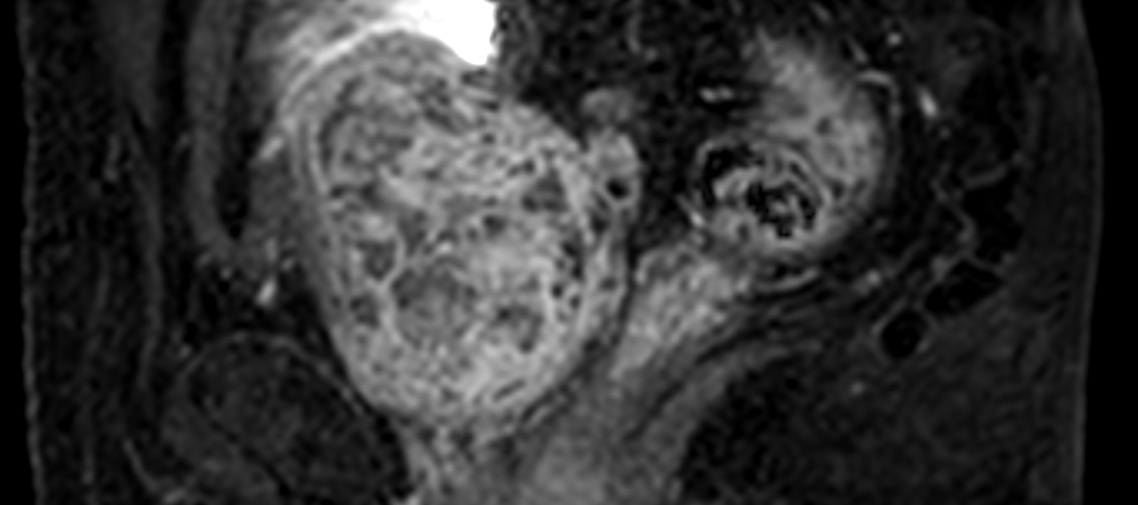

4D FreeBreathing

-